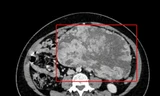

Bệnh nhân được chuyển đến Bệnh viện Xuyên Á. Tại đây, kết quả kiểm tra hình ảnh cho thấy bệnh nhân có khối u bì buồng trứng bên trái với kích thước khoảng 6cm. Sau hội chẩn, các bác sĩ đã quyết định phẫu thuật nội soi cắt bỏ triệt để khối u.